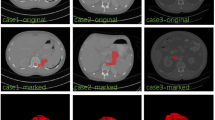

Automatic organ segmentation is a prerequisite step for computer-assisted diagnosis (CAD) in clinical application, which can assist in diabetes inspection, organic cancer diagnosis, surgical planning, etc. However, segmenting tiny organs like the pancreas is very challenging. Despite the success of convolutional neural networks (CNN) in automatic pancreas segmentation, the loss of the shape features impedes progress in clinical applications. Therefore, a novel pancreas segmentation network is proposed to extract features in a propagation and fusion manner, named FPF-Net. Firstly, the low-level features and high-level features are combined progressively to preserve and propagate the shape features of the pancreas. Secondly, instead of context-unaware addition or concatenation, we adopt attentional feature fusion (AFF) to alleviate the problems caused by the shape diversity and small size of the pancreas. Finally, a module consisting of Coordinate and multi-scale spatial attention (CMSA) is designed to exploit long-range dependencies and multi-scale spatial features. This module is used to extract salient information for pancreas segmentation. Experimental results validated on two pancreas datasets and a spleen dataset justify the superiority and generalization ability of our method and guarantee the reliability of our approach in clinical application.

Chen, H., Liu, Y. & Shi, Z. FPF-Net: feature propagation and fusion based on attention mechanism for pancreas segmentation. Multimedia Systems 29, 525–538 (2023). https://doi.org/10.1007/s00530-022-00963-1